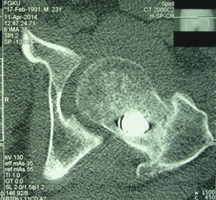

Уважаемые коллеги, приношу извинения за перерыв в работе -

был в командировке. За это время больному сделали КТ и,  сегодня,

снимки. Укорочение конечности - 1-1,5 см, ШДУ-115 градусов, замедленная консолидация,

остеопороз.

Вопрос о тактике дальнейшего ведения пациента (напоминаю, возраст 19

лет)?